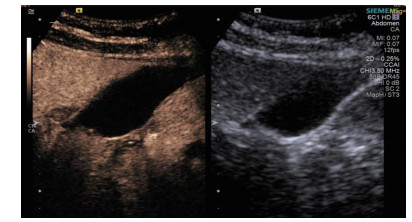

1.3 手术过程 1.3.1术前经肘静脉超声造影:行PTGBD前半h经肘静脉快速团注SonoVuel 5 mL,在对比脉冲序列造影成像模式下进行观察,根据不同组织造影剂凝聚的时间及浓度差异,判断胆囊周围组织黏连程度、胆囊壁完整程度(图 1),如出现胆囊壁造影剂充盈缺损(图 2、3),则考虑胆囊壁坏死或穿孔,根据静脉造影情况选择合适的置管入路,避开胆囊穿孔的部位及黏连组织。

| 图 3 经引流管造影胆囊超声显像,二维图像(左),造影图像(右) |

术后再次经肘静脉超声造影同时经引流管超声造影:PTGBD后,再次经肘静脉快速团注SonoVuel 2 mL,在造影成像模式下进行观察肝脏被膜、胆囊床穿刺路径有无造影剂外渗,腹腔内有无外渗凝聚的造影剂,判断有无活动性出血及出血程度,如判断出血速度快、出血量较大,考虑动脉性出血,及时改为开腹或腔镜手术止血。PTGBD术后经引流管超声造影,置管成功后快速抽出胆囊内残留胆汁,减轻胆囊压力后,在超声造影模式下直接经引流管注入配制待用的稀释声诺维造影剂20 mL,实时动态的观察造影剂在胆囊腔内的充盈范围(图 2、3),评估引流管的通畅程度及引流范围、观察其在胆囊腔内的位置走形及卷曲情况、观察胆囊周边及腹腔内有无造影剂外渗。如患者腹痛症状加剧,结合经引流管超声造影判断有胆汁漏出表现,应持续监测观察患者生命体征及保守治疗效果,必要时及时改行开腹或腔镜手术治疗。

超声造影是利用超声造影剂微泡(本组应用的是声诺维超声造影剂微泡)在低机械指数声波照射下发生共振,产生线性及非线性谐波回声信号,形成造影增强图像的技术,是近年来新兴的超声技术,具有实时、可连续观察、无辐射、可重复性好、毒不良反应少等优势,为临床提供了全新的诊疗手段[14]。经肘静脉注入的标准配置超声造影剂是一种血池造影剂,可以反映组织的血流灌注情况同时亦被广泛应用于肝、脾、肾等实质性脏器破裂的诊断,其诊断的敏感性及特异性均明显优于二维超声,且与增强CT有较好的一致性[15-16]。本组病例术前经肘静脉注入标准配置造影剂后,胆囊壁均显影增强,胆囊穿孔及周边积液处表现为造影无充盈区,穿刺置管后再次静脉路超声造影,迅速发现术后出血部位且可敏感评估是否为活动性出血(经手术证实)。除1例因活动性出血中转腹腔镜手术外,其余32例置管成功后经引流管口注入稀释造影剂20 mL(1:200稀释),评价引流管位置、引流范围及是否出现胆汁外漏取得良好效果,所有引流导管均能够清晰显示引流导管置入路径、引流管形态及引流范围,引流管置入恰当者,头端位于胆囊内,全管显影清晰,造影剂弥散区域与胆囊大小吻合; 置管后胆汁漏出者,可见造影剂沿引流管周边渗出[17-18],本组中3例出现造影剂外渗,其中两例渗出范围局限于胆囊床附近,未渗出至游离腹腔,患者腹痛症状稍有加剧,经胆囊减压及对症处理后好转,其中1例见造影剂渗出至肝肾间隙,患者腹痛症状加剧明显,考虑置管位置不当,余行急诊腹腔镜手术治疗,术中证实为系膜胆囊,且可见引流管侧孔部分外露。笔者的经验是,术前选择静脉路超声造影有助于对胆囊情况的评估及穿刺点的选择,术中正确选择穿刺针的入路有利于提高穿刺引流的成功率。首先是胆囊穿刺部位的选择应选择在靠近胆囊颈侧,此处胆囊位置比较固定,受体位影响较小,且胆囊床结缔组织较为固定,有助于将漏出胆汁包裹局限,其次是进针方向与胆囊床尽可能保持垂直,减少进针位置的偏移,同时置管成功后应即刻尽量抽尽胆囊内的感染性胆汁,生理盐水冲洗后行经引流管稀释超声造影有助于判断置管位置、引流范围及是否出现胆汁漏出,减少不必要的并发症发生率。穿刺引流后可以根据患者的营养状况待窦道形成稳定后择期拔除引流导管。对全身情况改善适合手术治疗且有手术意愿者可以考虑择期胆囊切除术。